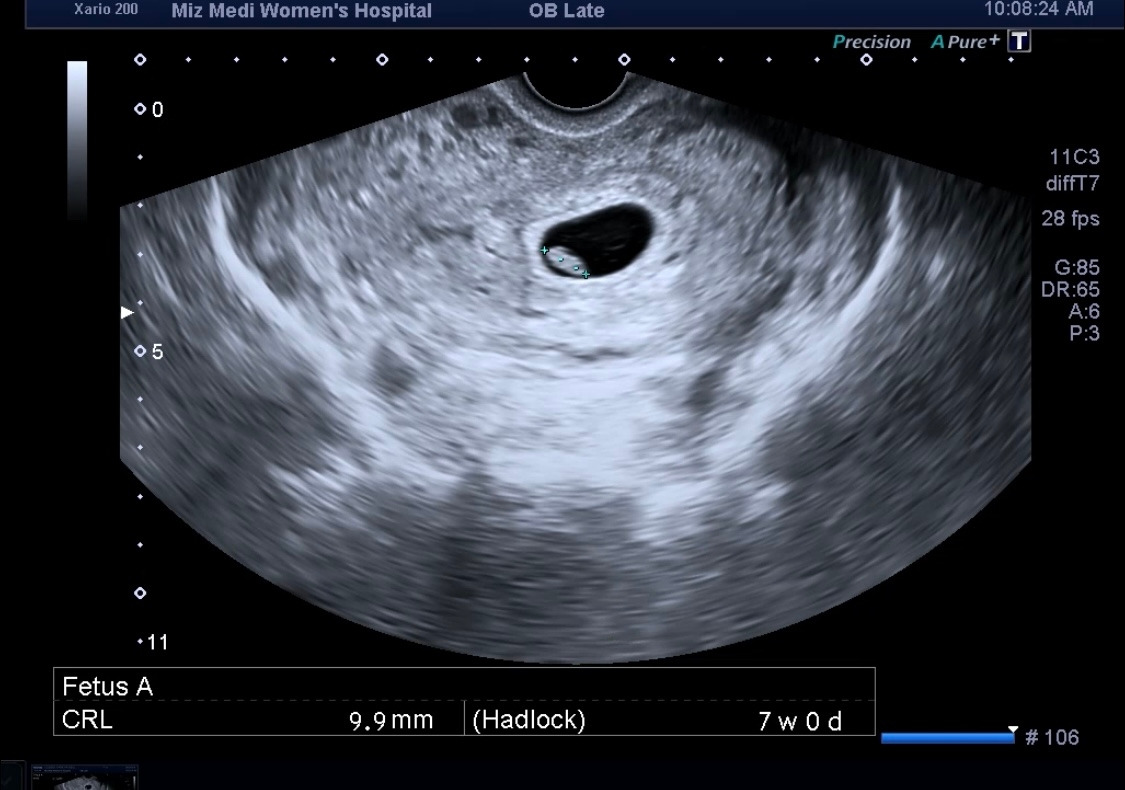

7주 차 0일에 방문했을 때는 정말 콩알만 한 아가가 보였다. 10mm 저렇게 작은 생명체에서 들리는 심장소리란 그때의 느낌은 참으로 신기했었다. 그리고 2주 만에 이렇게 머리, 몸, 팔, 다리가 보이는 아가로 성장하다니!

이제 2.3cm 정도 2배가 되었고 2등신이 되었다.

피 비침도 없고 양쪽 난소도 좋고, 이제 유산 가능성은 낮다고 말해주셔서 더더욱 마음이 놓였다.

심장소리는 더욱 크고 빨라진 거 같았다. 의사 선생님께서 너무 빠르니 놀라지 말라고 미리 말씀을 해주셨다. 아가들은 일반 성인보다 훨씬 심장박동이 빠르다고 하셨다. 아마도 몸이 작으니 그만큼 더 많이 움직여야 하나 보다라고 생각을 했다.